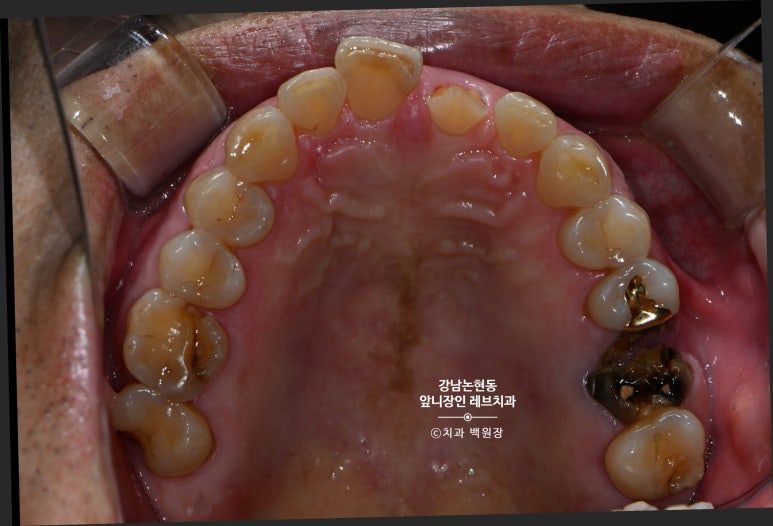

그런데 말입니다? 교합면에서 보면 꽤나 치아가 많이 남아보인단 말이지요.

입천장쪽 면에는 꽤나 치아가 남아있는것을 보실 수 있습니다.

치아 머리가 너무 많이 없어지면,

신경치료 하고 기둥을 심어야 합니다.

짧아져버린 치아부러짐을 해결하기 위해서 의도적으로 신경치료를 하게 되었습니다.

이는 치아에 기둥을 심기 전에, 반드시 해야하는 치료입니다.

신경치료는 치아 안의 신경을 제거하고, 재료를 채워넣는... 사실 치아의 생명을 뺏는 행위입니다만.

도리어 이 치아를 살리기 위해 기둥을 심어야하고 기둥을 심기 위해 신경치료를 하는 상황입니다.

신경치료를 잘 마무리하고나서 앞니를 찍어보았습니다.

거의 무에서 유를 창조한 셈인데요.. 저 남아있는 치아 안에 굵직한 기둥이 심겨져 있습니다.

잘 보시면 뿌리쪽에 약간 어두운 치아가 있는데, 그것이 본래 갖고 계신 자기 치아이고,

보다 밝은 색으로 대부분을 이루고 있는 부분이 기둥 (fiber post) + 레진 코어 (resin core) 입니다.

그리고 많이 티는 안나지만, 대칭되는 가운데 앞니와 최대한 비슷하게 만들기 위해 잇몸 경계도 성형해줍니다.

씹는 면에서 보면 꽤나 깊이 치아의 경계가 형성된 것도 확인할 수 있으실겁니다.